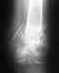

Играл в футбол. Получил удар по стопе.

ну как получил, отбирал мяч - мяч отобрал и получилось так что подъемом (т.е. тем местом когда обычно по мячу бьешь, выше пальцев, но ниже голени (просто не знаю как правильно это место описать) попал в чужую ногу, во время матча нога не болела, на след. день боль была очень слабая и слегка припухло место ушиба. Через неделю все "как бы" прошло, т.е. болей почти не ощущал, но отек не до конца сошел - решил снова побегать и поиграть в футбол, все прошло нормально. НА след. день решил еще сыграть в футбол, во время мачта почувствовал боль во время бега, но терпимую, боль в районе сгиба большого пальца на левой ноге, теперь там болит, но болит терпимо.На мысочки встать могу - не больно при ходьбе, скажем, с 30-го метра начинает появляться боль на сгибе большого пальца левой ноги.Что бы это могло быть, просто ко врачу никак не получается попасть:(